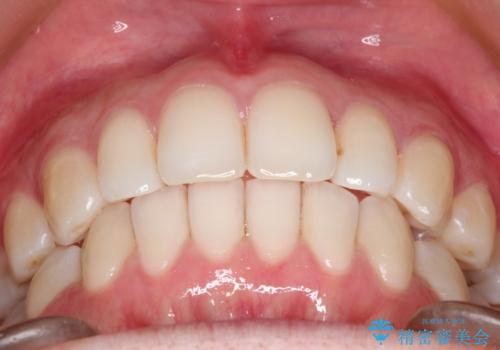

内側に入り込んでしまっている歯を出してくることに非常に時間がかかりましたが、一度歯を歯茎の方へ押し込みそして前へ出してくる2段階の治療を行いました。

見た目、嚙み合わせ及び、治療期間や施術内容に大変ご満足いただきました。